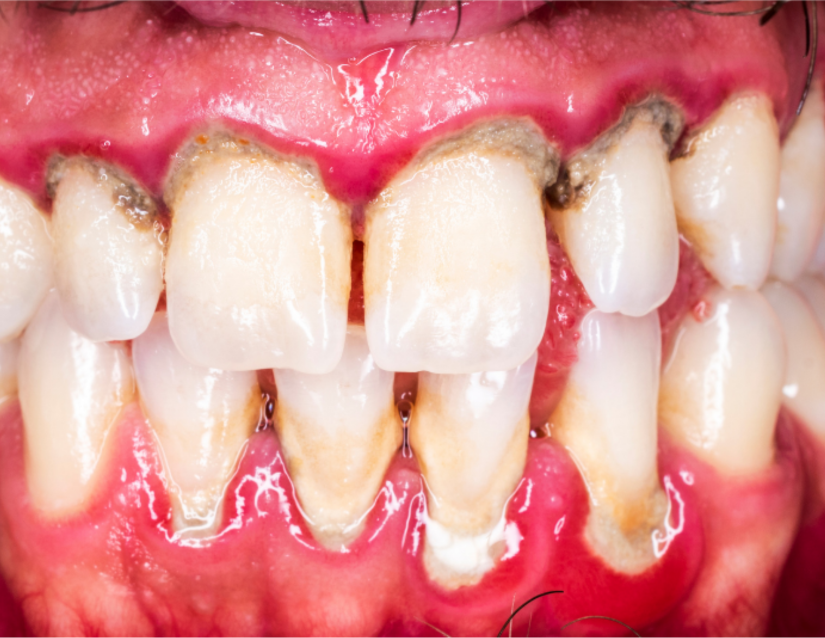

Periodontitis

etapa inicial enfermedad periodontal - Periodoncia - Clinica Dental Jardines

Ahora, la placa bacteriana y el sarro pueden dañar también otros tejidos, a las bolsas periodontales y afectar a la raíz del diente.